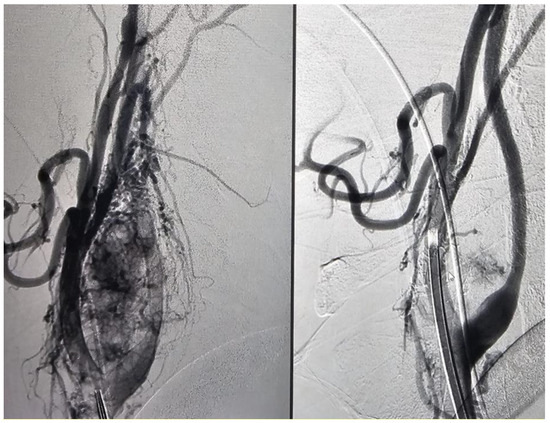

2.4. Angiographic Evaluation

3.4. Primary Outcome: Effectiveness of Embolization

4.1. Embolization with Onyx

4.2. Particle Embolization